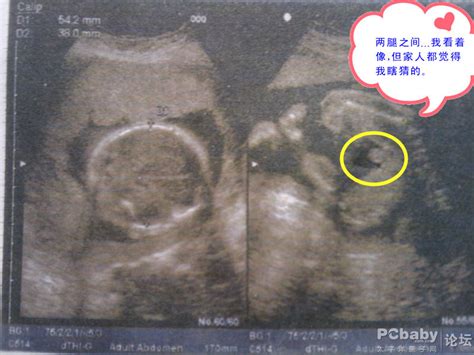

PBD 双顶径 胎儿头的两顶骨之间的最大距离HC 头围AC 腹围FL 股骨长度AFV 羊水指数 以脐水平线和腹白线为标志将子宫直角分成四个象限,测量各象限最大羊水池的垂直径线,四者之和即为羊水指数